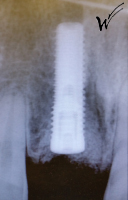

L’implant a été positionné dans l’alvéole, aligné avec la racine. À ce stade, un guide chirurgical peut s’avérer extrêmement utile, en particulier pour éviter d’éventuels obstacles anatomiques, tels que des paquets vasculo-nerveux situés dans le trou rétro-incisif.

Après la guérison des tissus mous (gencive) et durs (os alvéolaire), la couronne céramique esthétique a été installée sur l’implant.